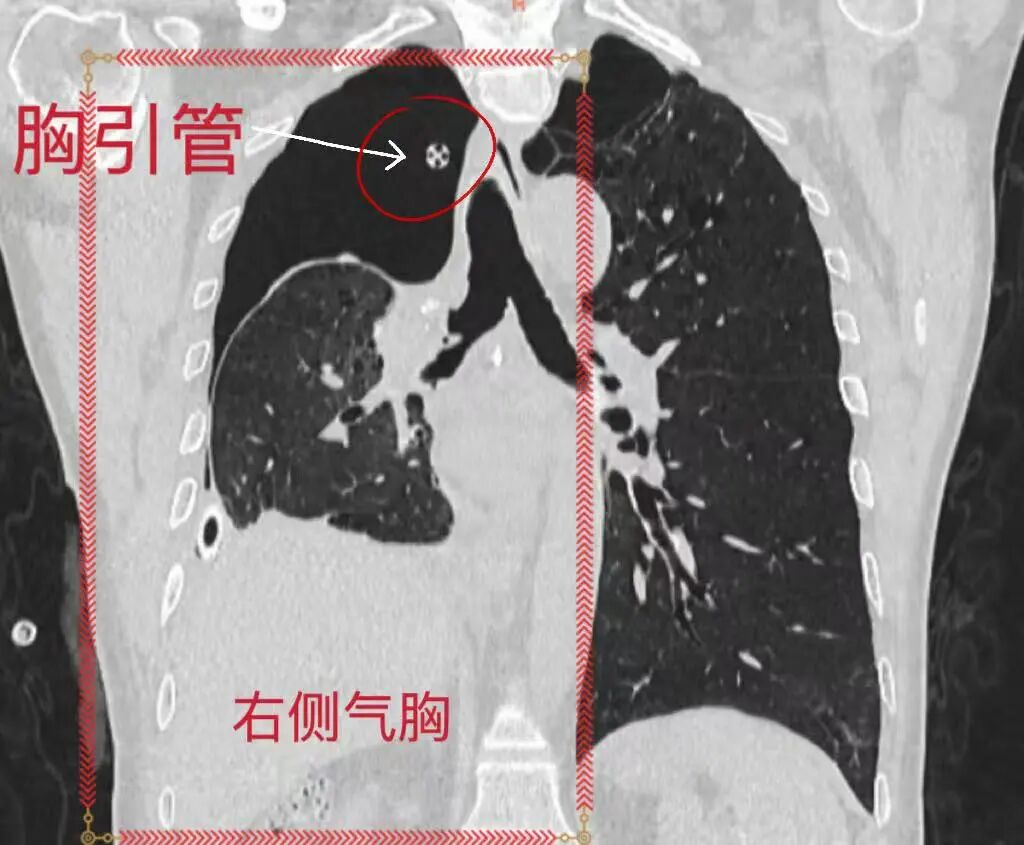

【厚德精医】微创 “杂交” 手术,一站式解决双侧肺部“高危”结节难题